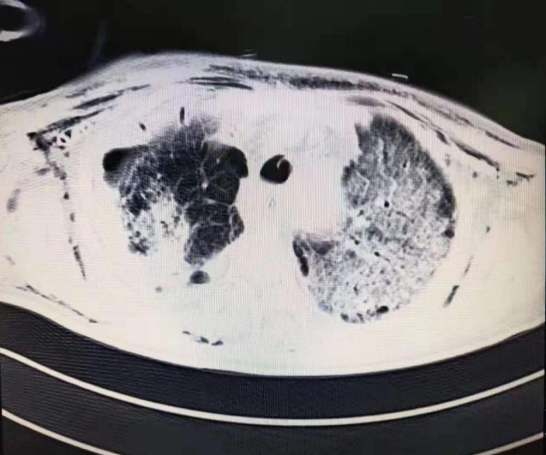

凌晨时分,一名重症患者病情恶化发展为ARDS,血氧含量急剧下降,呼吸循环极差、缺氧严重。给予呼吸机最大支持力度,氧合指数仍一度低于70mmHg(氧合指数正常值为400-500mmHg),循环支持药物使用已接近极量,有效循环仍无法维持,严重酸中毒难以纠正……眼看着患者病情还在继续恶化,如果没有有效的救治方式,生命之火将因缺氧而熄灭。

随着设备的运转,静脉血由离心泵(人工心脏)从股静脉里抽出,经氧合器(人工肺)氧合并排出二氧化碳后,又泵回颈静脉,为患者严重病变的肺串联了一个人工肺,让不堪重负、岌岌可危的肺得到了充分休息,开始自我修复。患者的外周血氧饱和度也从之前的70%迅速上升到100%,氧合指数逐渐趋于正常,各种循环支持药物逐渐减量……经过2个多小时争分夺秒的抢救,以及一整夜连续不断的监测,患者病情有效好转。